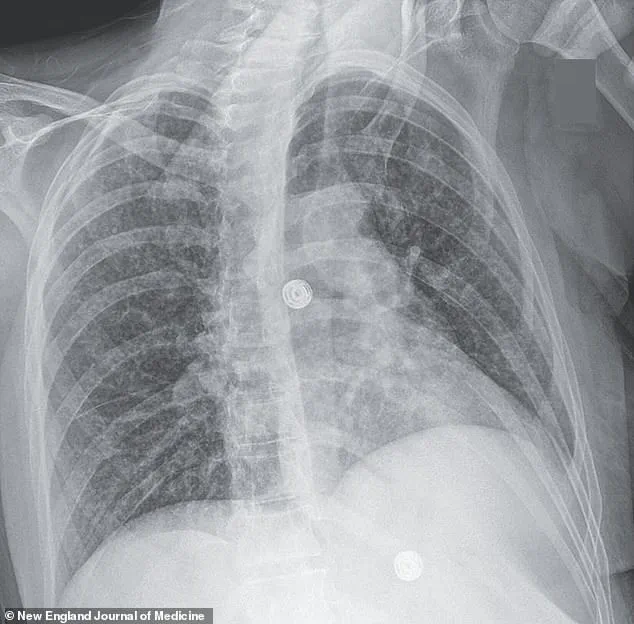

A harrowing case study illustrates the devastating consequences of undiagnosed and untreated TB.

A woman’s medical scans revealed nodules in multiple organs, including her lungs, liver, pancreas, and brain.

Her journey through the healthcare system was fraught with complications, including a 33-day hospitalization for antibiotics, steroids, and antiretroviral therapy to combat HIV.